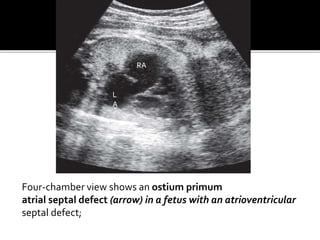

Four-chamber view shows an ostium primum

atrial septal defect (arrow) in a fetus with an atrioventricular

septal defect;

Four-chamber view showsan ostium primum atrial septal defect (arrow) in a fetus with an atrioventricular septal defect; L A RA